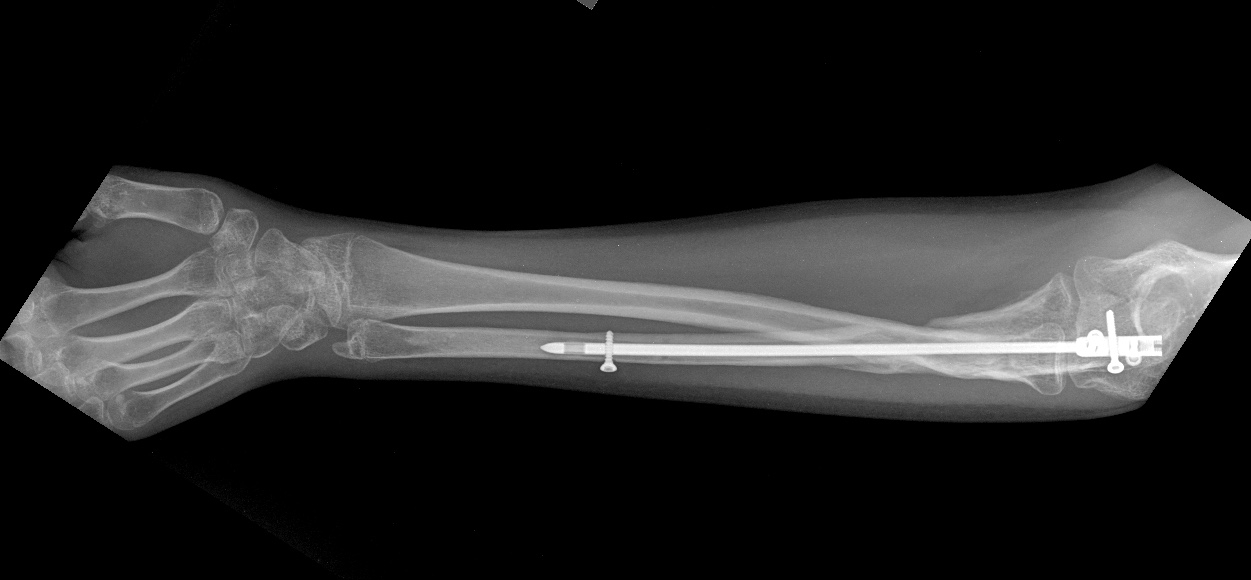

псевдоартроз локтевой с застарелым вывихом радиоульнарного сочленения |

Оперирована около 1 года назад. Радиоульнарное сочленение было вправлено, фиксировано спмцей, спица удалена. На сегодня имеем такую картинку. Работает водителем трамвая.Что посоветуете в этом случае? Восстановить длину локтя - это понятно. как лучше поступить с радиоульнарным сочленением?

Мы бы удалили пластину. Аппаратом постепенно восстановили бы взаимоотношения. И заштифтовали бы локтевую кость, смоделировав стержень, чтобы он был напряжен в противоположную сторону тому, как сейчас выглядит локтевая кость, т.е. вогнутой стороной в сторону межкостного промежутка. Чтобы лучевая кость удерживалась натяжением межкостной мембраны. Пример в приложении. Тут был более свежий случай, поэтому вправилось одномоментно.